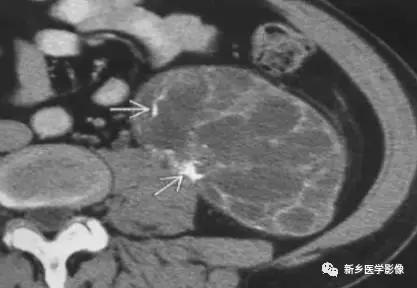

肾脏肿瘤

主要包括合并钙化的常见肿瘤或肿瘤样病变,如:肾囊肿,肾细胞癌,多房囊性肾瘤,多囊肝多囊肾囊壁钙化,肾脏结核,肾脏钙乳症